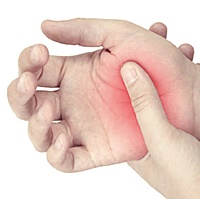

류마티스 관절염 초기증상 3. 관절 홍조와 붓기

류마티스 관절염이 발생하면 손과 발의 관절 주변 피부가 붉어지고 부어오를 수 있습니다. 이러한 관절의 홍조와 붓기는 시각적으로 확인할 수 있는 초기 증상입니다. 부어오른 관절이 며칠 동안 지속되거나 치료가 필요할 정도로 악화될 수 있으므로, 빠르게 진단을 받고 치료를 받는 것이 중요합니다.